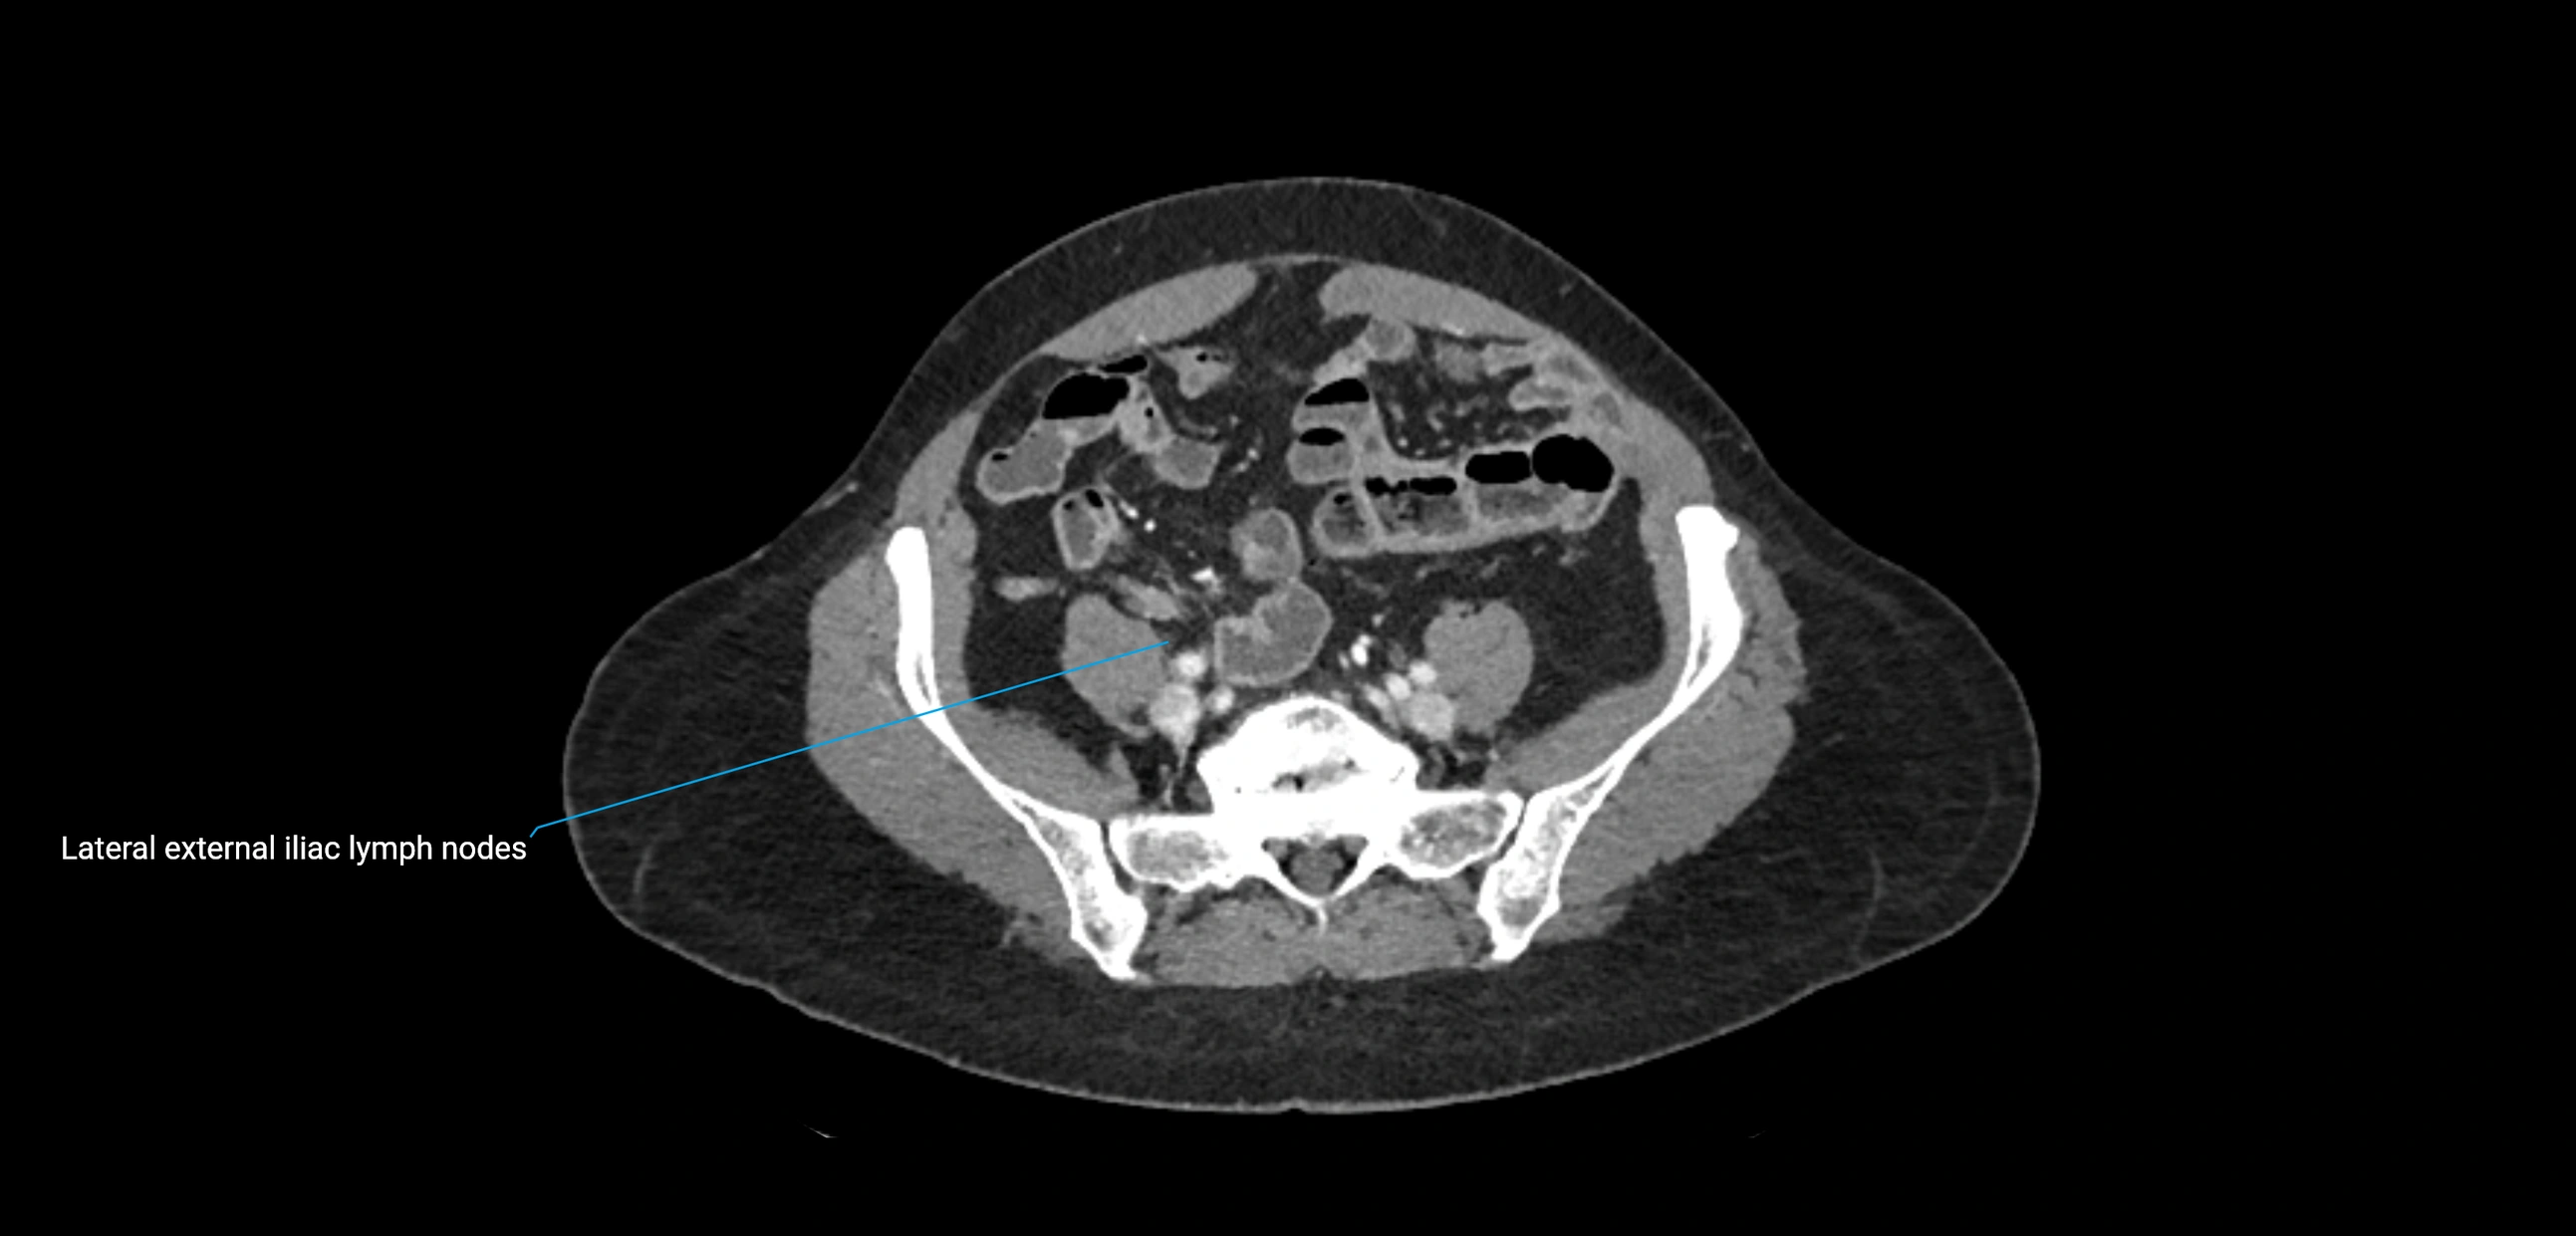

CT image

image